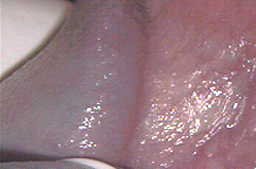

Desde hace muchos años se ha observado que si la piel infectada por Virus del Papiloma Humano (piel con lesiones o infectada) es destruida, se regenera con piel sana y el paciente puede eliminar la infección con una tasa de éxito variable dependiendo del tipo de aparato usado, y de la mejora que se obtenga en el sistema inmunológico de cada paciente.